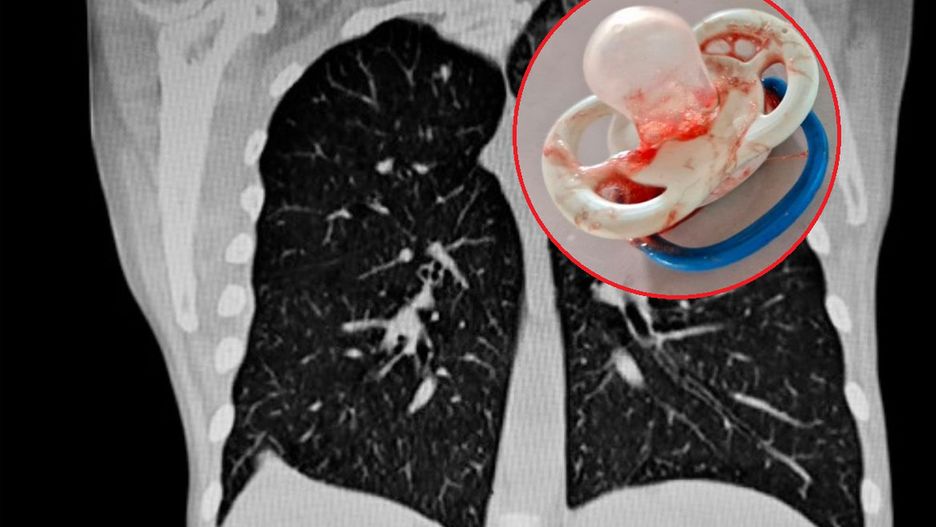

Dzięki błyskawicznej reakcji ratowników medycznych z Wojewódzkiej Stacji Ratownictwa Medycznego (WSPR) w Łodzi udało się uratować życie siedmiomiesięcznego dziecka. Dziewczynka zachłysnęła się smoczkiem. Przedmiot blokował wejście do tchawicy.

- Ratownicy zastali matkę trzymającą na rękach dziewczynkę. Objawy, jakie prezentowało dziecko, wskazywały na ciężką niedrożność dróg oddechowych. Okazało się, że niemowlę zachłysnęło się smoczkiem - relacjonuje rzecznik łódzkiej WSRM Adam Stępka cytowany przez portal se.pl.

Stępka tłumaczy, że przedmiot blokował przepływ powietrza przez drogi oddechowe, co mogło doprowadzić do śmierci dziewczynki.

- Ciało obce w drogach oddechowych może całkowicie zamknąć światło krtani lub znajdującej się dalej tchawicy. Wówczas pierwszymi objawami jest kaszel, będący odruchem obronnym. Na skutek zablokowania przepływu powietrza dochodzi również do sinicy - podnosi Stępka.

- Ratownicy umieścili w jamie ustnej dziecka laryngoskop - urządzenie uwidaczniające wejście do krtani i przy pomocy specjalnych kleszczyków usunęli smoczek blokujący wejście do tchawicy - dodaje rzecznik łódzkiej WSRM.

Po usunięciu smoczka z dróg oddechowych stan dziecka poprawił się. Jednak dziewczynka musiała zostać przewieziona do szpitala.